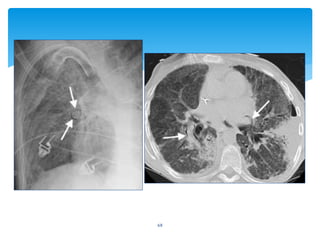

68

69